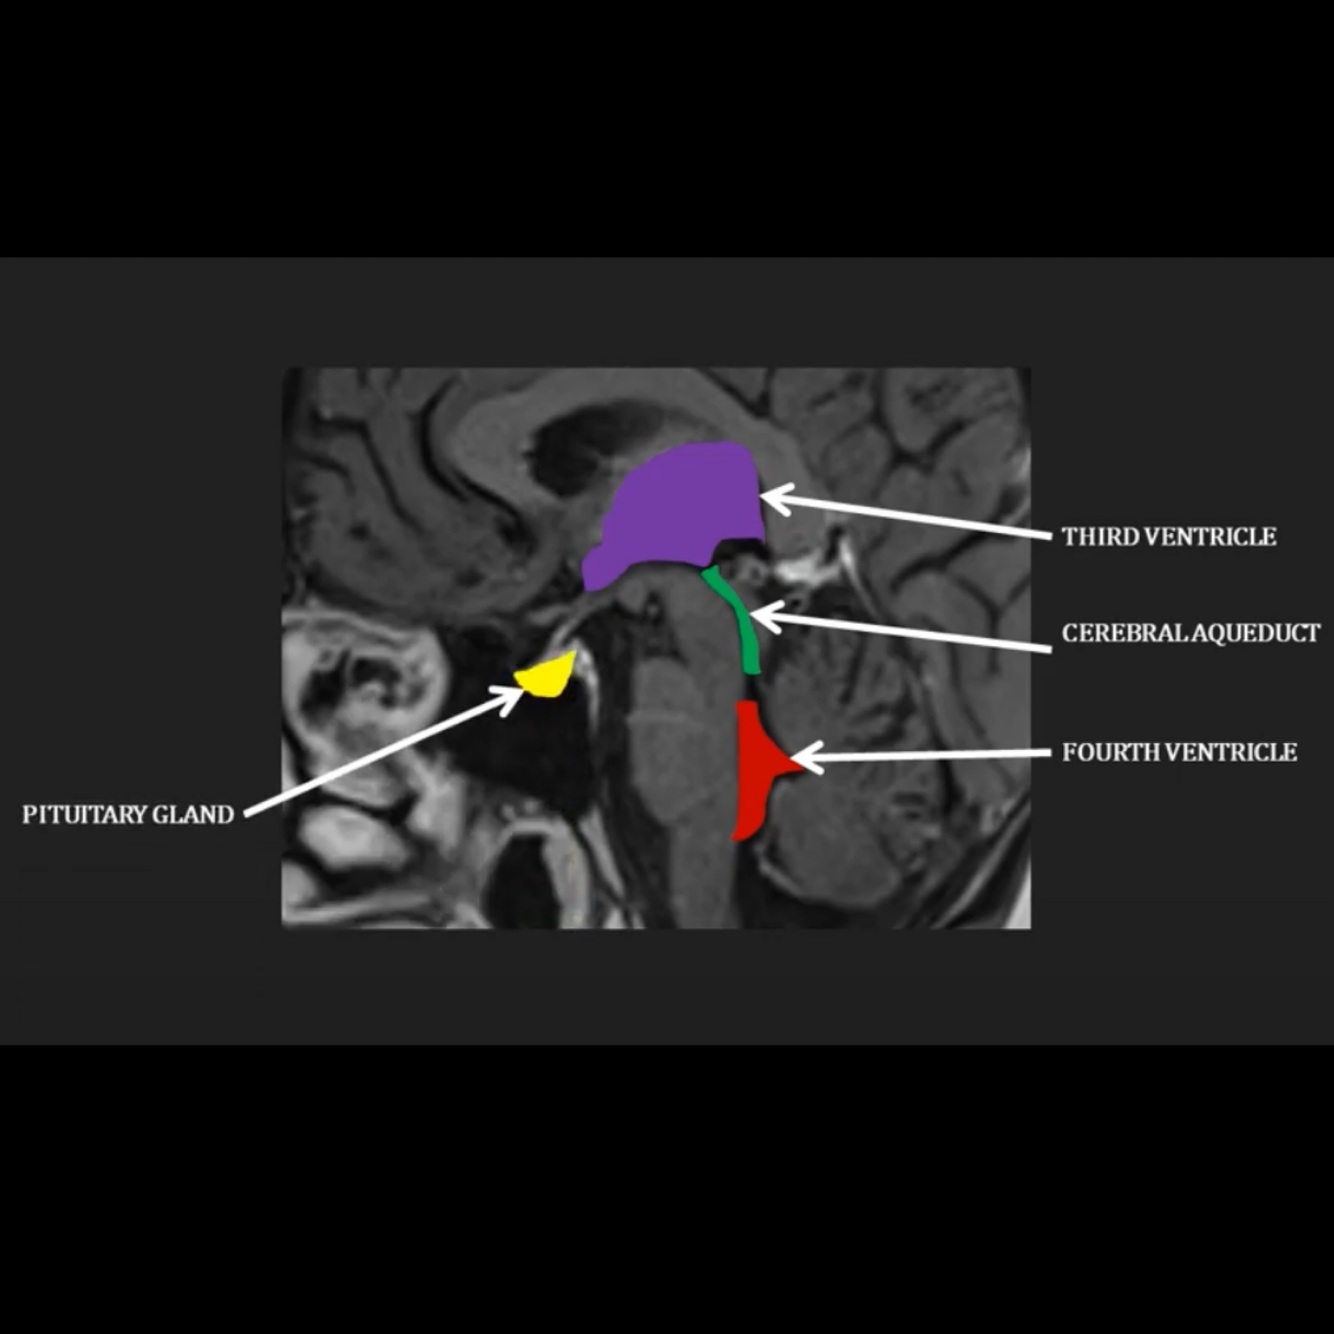

Where does the CSF flow through the brain as visible on this diagram?

Through the third ventricle into the cerebral aqueduct, into the fourth ventricle

Where does the pituitary gland sit in relation to the ventricles?

Anteriorly in the pituitary fossa